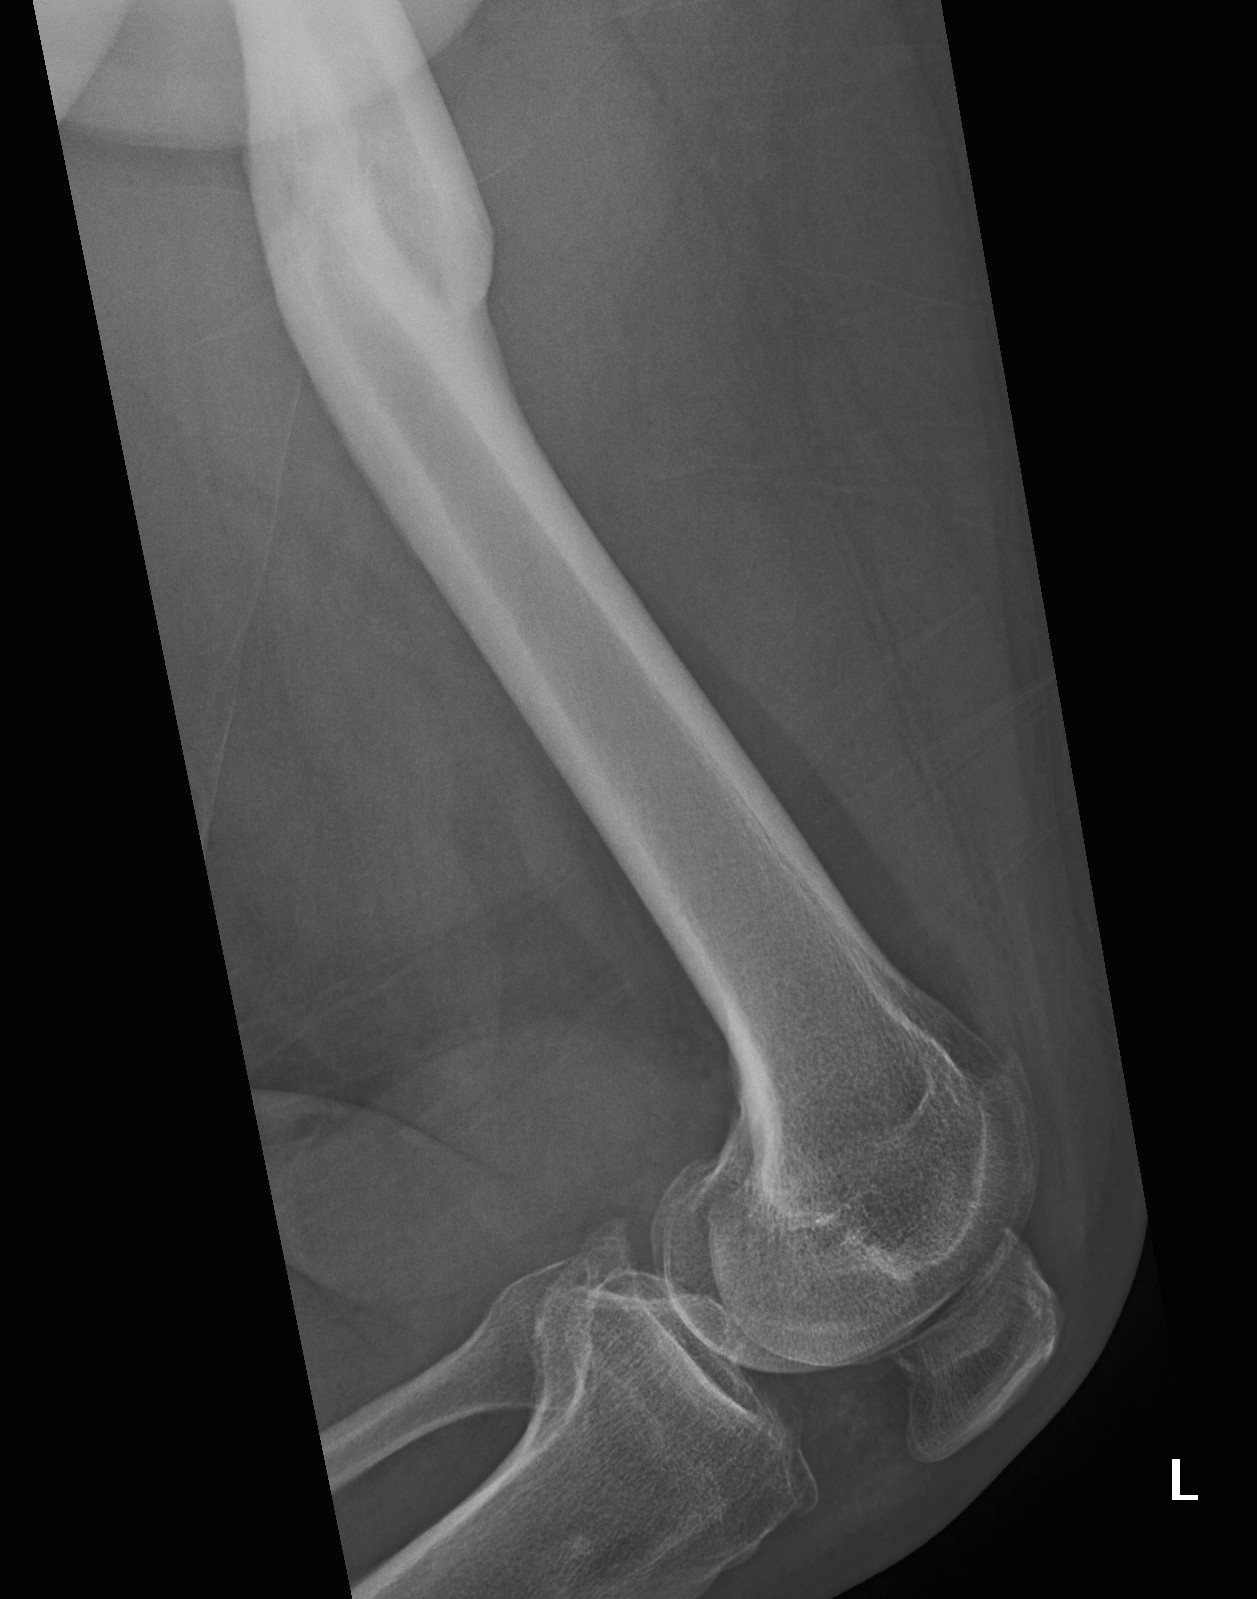

Fracture Malunion

A. Femoral Osteotomy

B. HTO